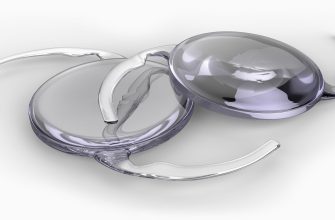

Lens dislocation, also known as dislocated lens, is